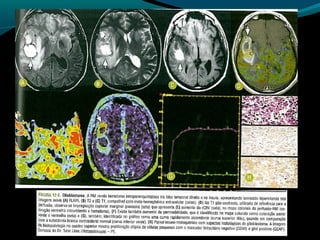

Glioblastoma

Maligno;

Origem astrocítica;

Grau IV;

60% dos astrocitomas;

15% das neoplasias intracranianas;

Mais frequente em adultos;

Sobrevida de 9 a 12 meses;

TC:

Geralmente supratentorial;

Infiltra substância branca;

Processo expansivo iso ou hipodenso de limites mal

definidos e necrose central;

Pode apresentar hemorragias;

Calcificações são raras;

RM:

Sinal heterogêneo em T1, T2 e FLAIR; (necrose, cistos,

hemorragia, neovascularização); mas predomina

hipointensidade em T1 e hiper em T2 e FLAIR;

Realce difuso e heterogêneo pelo Gd;

Redução do NAA

Aumento do Co

Redução da razão Mi/Cr

Picos de lipídeos e lactato

Centro necrótico não restringe à difusão;

Na perfusão: aumento do CRBv máximo;

OBS: capacidade invasiva impede ressecabilidade total;